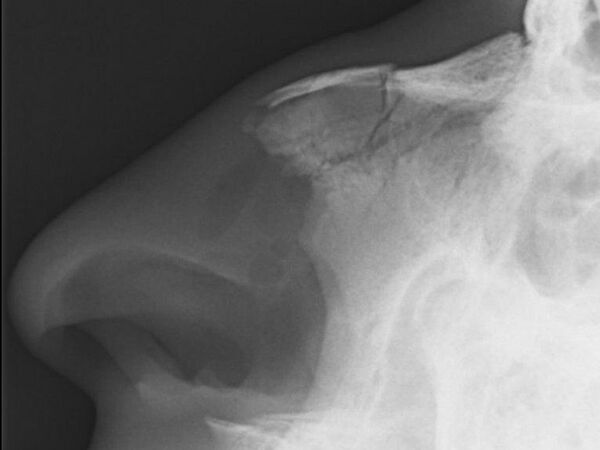

При травмах в области лица и переломах носа повреждения носовых костей носят наиболее частый характер[3], при этом возможны смещение костей, расхождение швов или переломы[4][5].